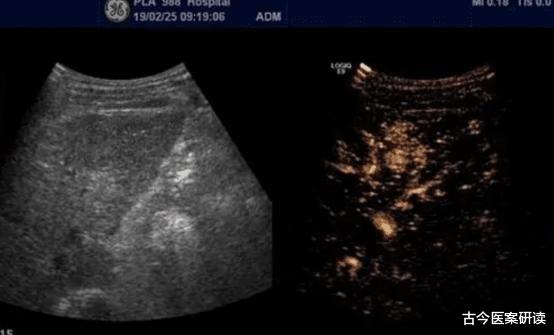

经过全面身体检查 , 在肝CT的影像中 , 发现肝内有一个8公分的肿瘤 , 确诊晚期肝癌 。